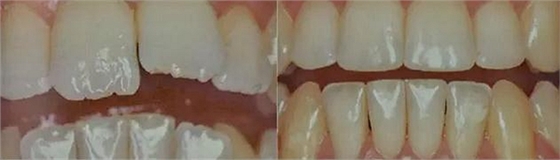

十、最后放一個鄰面去釉實例:

鄰面去釉前 鄰面去釉后